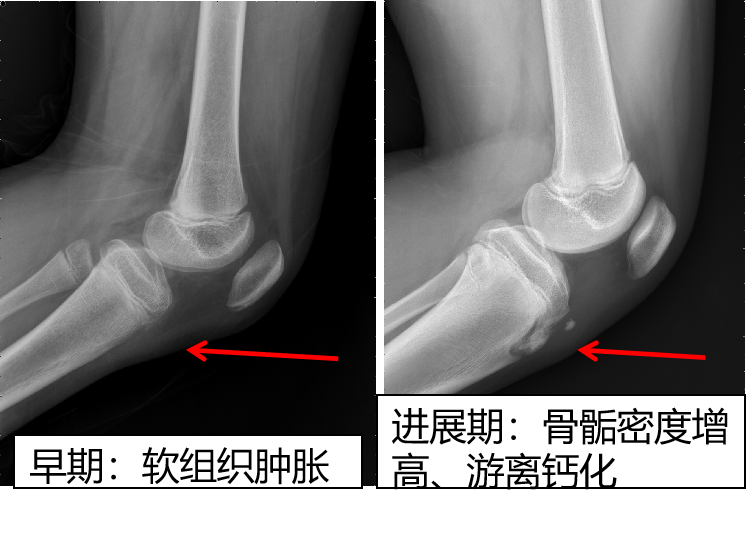

胫骨结节骨骺炎的主要X线检查表现为:1.局部软组织肿胀、密度增高。2.异位钙化;由于局部既有骨的坏死又有新骨的形成,特别是股四头肌附着点或肌腱处继发性钙化或者异位钙化。3.骨骺的改变;表现为骨骺密度增高,边缘不规则,部分骨骺破碎、分离。

早期,仅表现为胫骨结节处软组织肿胀,密度增高。进展期,可见部分胫骨结节软骨撕脱,或出现游离骨碎片。愈合期,可见胫骨结节骨性愈合或游离骨块硬化,软组织水肿吸收。